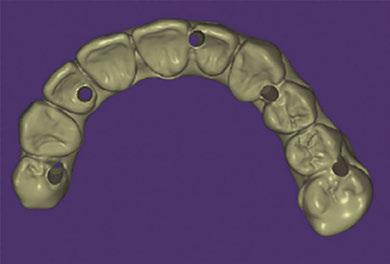

Step 3: Prosthesis fabrication

Once the photogrammetry scan is complete, a digital file extension (STL or XML file) is created that contains all the interrelated information on implant geometries, interfaces, healing abutments, and screws. This data can then be uploaded to CAD software to allow for digital alignment pairing and designing of the prosthesis.

These records are then exported into a design software (e.g., Exocad, 3Shape) where they will be merged to facilitate the design of an All-On-X prosthesis. All three of these methods can be utilized to align data to help record the vertical dimension as well as establish the ideal tooth position.